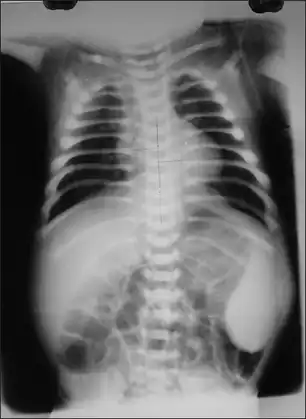

X-ray showing increased density in all the bones-Malignant infantile osteopetrosis